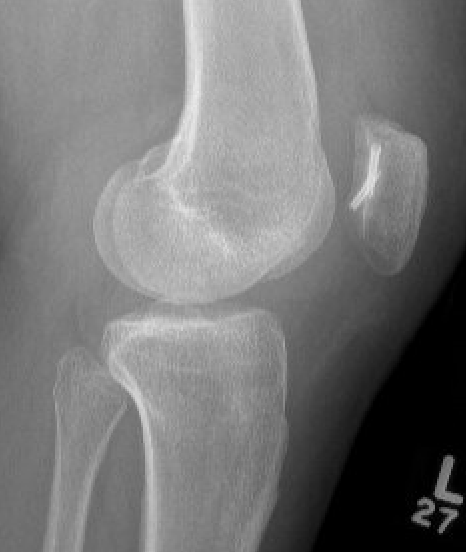

Xray

Look for osteochondral fractures

- AP xray: gutters

Loose body in lateral gutter